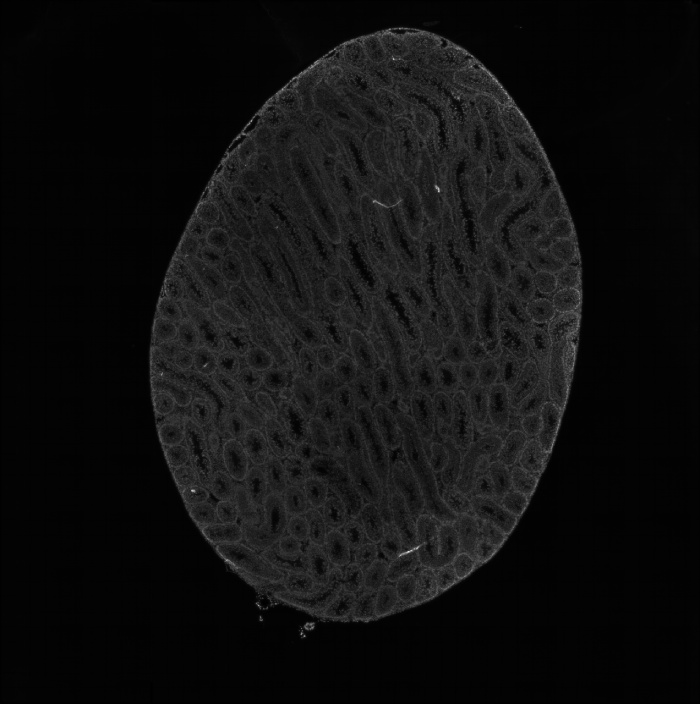

組織umi-count統(tǒng)計圖

圖2 組織UMI count統(tǒng)計圖